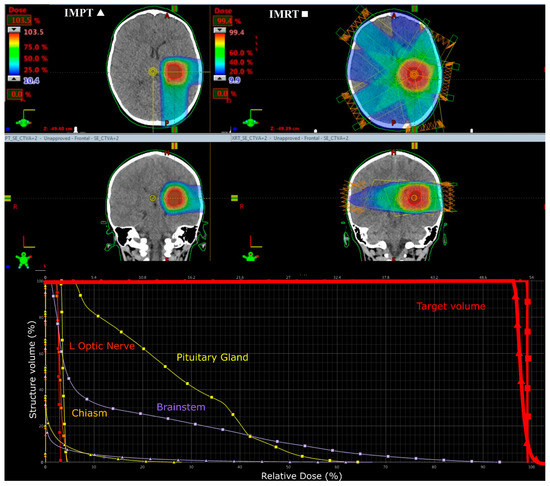

2.2.1. Prescribed Dose and Beam Arrangement for Intensity-Modulated Proton Therapy (IMPT)

2.2.2. Prescribed Dose and Beam Arrangement for Intensity-Modulated Photon Therapy (IMRT)

3.2. Supratentorial Ependymoma